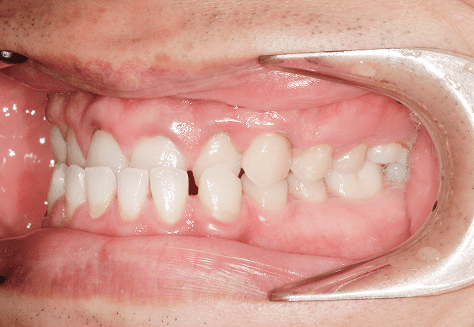

S.K

治療前

治療後

主訴

歯が重なっていて気になる。前歯が出ていて唇が閉じにくい。ハミガキがしにくい。

診断

上顎前突・叢生

年齢/性別

20代/男性

抜歯部位

上下第三大臼歯

使用装置

上下インビザライン

保定装置

上下ビベラリテーナー

診察料金

1,100円×33回

治療期間

3年5カ月